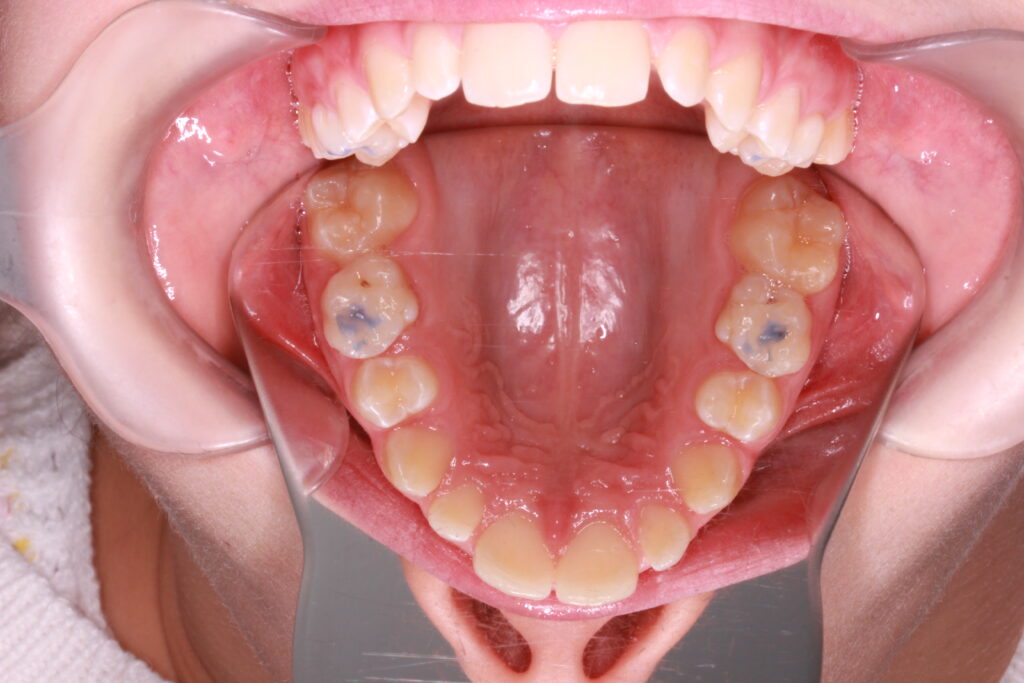

Az ALF készülék nem az agresszív erőhatásokra, hanem a funkcionális erők finom, biológiailag kíméletes irányítására épít. A klinikai tapasztalatok szerint ez tökéletes elég és mind a fogív fejlesztésében, keresztharapások megszűntetésében, helyteremtésben mind a nyelvtér növelésében jól működik.

A leggyakoribb a vegyes fogazat időszakában (6–11 év), de alkalmazható teljes tejfogazatban is nagyon korai kezelések esetében, akár 3-4 éves kortól is.